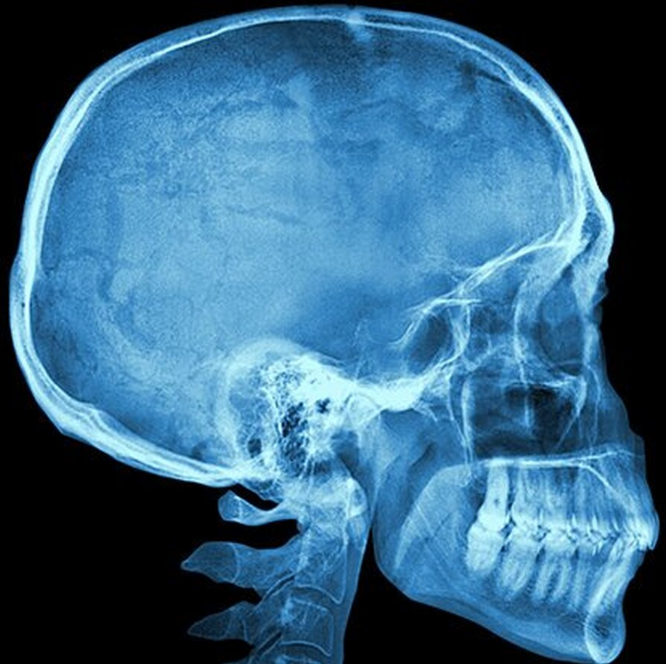

Анатомическая гармония: золотое сечение в черепе человека

Соотношение между узловыми точками нашего черепа образует золотое сечение — загадочный паттерн, связывающий множество вещей и явлений Вселенной.

Ученые сравнили черепа разных существ и пришли к выводу, что размер и форма черепа человека — это результат золотого сечения, всемирно известного «алгоритма красоты».

«Развиваясь на протяжении тысячелетий, человеческий череп воплощает элегантную гармонию структуры и функциональности», — пишут они в своей статье. Ученые сравнили 100 физиологически нормальных человеческих черепов с 70 черепами представителей других биологических видов. Особый интерес вызвала так называемая полукружная линия носоглотки, которая сводит верхние полукружные линии в выпуклой точке, называемой «инион».

Еще одна точка-ориентир — это «брегма», место схождения двух швов — венечного и сагитального. Сами швы, в свою очередь, образуются на месте соединения разных костей черепа. Исследователи измеряли расстояние между брегмой инионом, потому что они соответствуют важным нервным структурам как у людей, так и у других существ.

Схема расположения иниона и брегмы в черепе человека

По словам исследователей, если вы разделите расстояние от брегмы до иниона на расстояние от носового соединения до брегмы, а затем разделите размер дуги в области носа на расстояние брегма-иниона, эти два числа образуют отношение примерно 1.6. Оно и в самом деле довольно близко подходит к стандарту золотого сечения, а потому исследователи заподозрили, что все это не просто так.